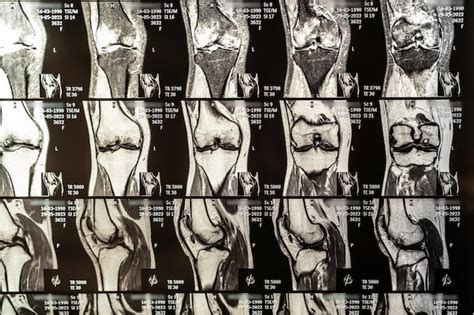

- Tomografía Computarizada (TC) y Resonancia Magnética Nuclear (RMN): Ofrecen mayor detalle que las radiografías. La RMN es especialmente valiosa para visualizar tejidos blandos como músculos, ligamentos y tendones. La TC es más rápida y expone a radiación ionizante, siendo las imágenes óseas su fortaleza.

- Ecografía: Cada vez más utilizada para identificar anomalías y inflamación en articulaciones y tendones, y como guía para procedimientos de inyección o aspiración articular.